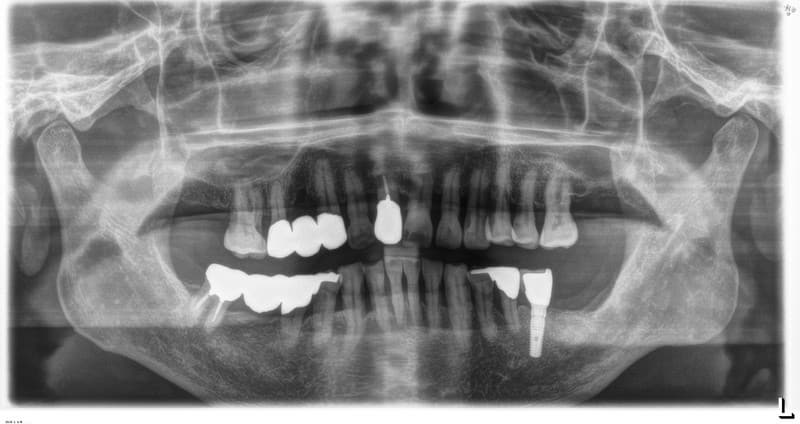

前歯部一本欠損の場合

従来の治療

両隣の健康な歯を削って土台にし、ブリッジで治療。

インプラント治療

欠損部にインプラントを埋入し、人工の歯を単独で装着。